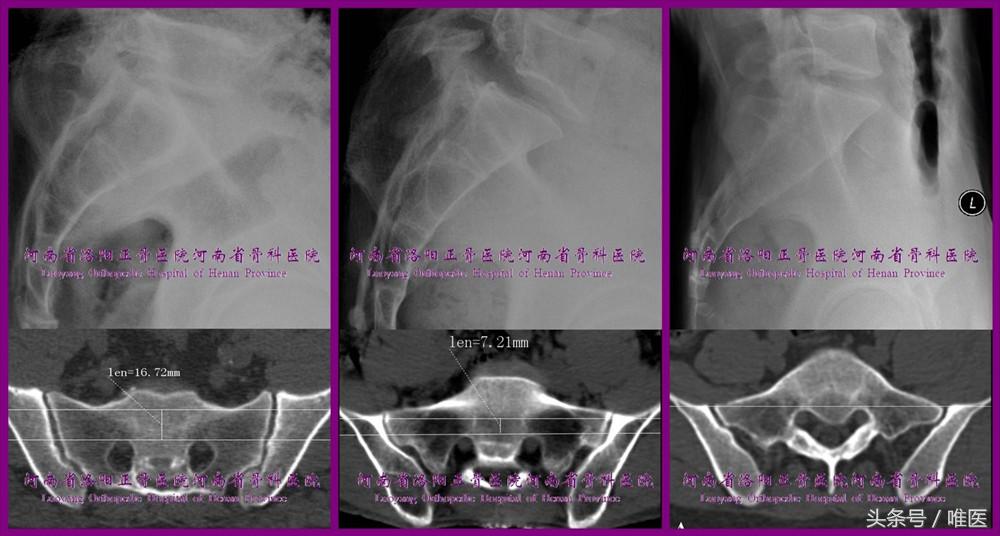

为了能更好的指导骶髂螺钉置入操作,蔡鸿敏等在轴向骨盆CT扫描的基础上,根据骶1节段是否存在平向螺钉通道及通道的大小对上骶段进行了分型[11]。(图3)

测量方法[12]:

①髂骨高密度线(iliac cortical density,ICD)[13]与骶骨翼斜坡(sacral alar slope,SAS)间存在有三种关系,即SAS高于、平于、低于ICD;

②SAS高于和平于ICD则以双侧ICD联线作为平向螺钉通道的前界,SAS低于ICD则以双侧SAS最低点联线为平向螺钉通道前界;

③双侧骶神经根管前缘联线为平向通道后界;

④前后界间的最短距离为平向螺钉通道的宽度;

⑤至少连续测量4个层面[14]。

1. 正常型

存在平向通道且宽度测量值均>7.3mm。有可以容纳平向骶髂螺钉的安全通道,也有宽敞的斜向通道,对骶髂螺钉偏差(相对于通道的轴)的容忍度较大。可根据具体的骨折类型置入平向或斜向骶髂螺钉。置钉操作相对较为容易,医源性损伤几率相对较小。

2. 过渡型

存在平向通道,但在扫描层面上其最大宽度值≤7.3mm。有限的平向通道可作为斜向骶髂螺钉的进钉点的选择区域。将进钉点确定于其内并结合骨盆出入口位确定好导针的头端、前方、内侧指向即可直接排除内置物对骶1神经根的威胁。

3. 变异型

不存在平向通道,即在所有层面扫描图像上平向通道均≤0mm(ICD联线与骶神经根管前缘相切时为零,通过骶神经根管时为负值)。于此型上骶段内置入斜向骶髂螺钉过程中,除非应用椎体侧块轴位像 [15]或非标准的骶骨侧位像[16],否则术中将没有任何直接的证据可证明内置物未损伤骶1神经根。故相对于其他两型,于变异型上骶段内置入骶髂螺钉的难度最大、危险性最高。另有研究证明,如果骶1骶段的斜向螺钉通道较小,则其骶2骶段常有相对宽裕的平向螺钉通道可用于置入骶髂螺钉[9,17]。因此,建议在变异型骶骨的骶2节段置入骶髂螺钉。

图3. 上骶段的分型。自左向右依次为正常型、过渡型及变异型。